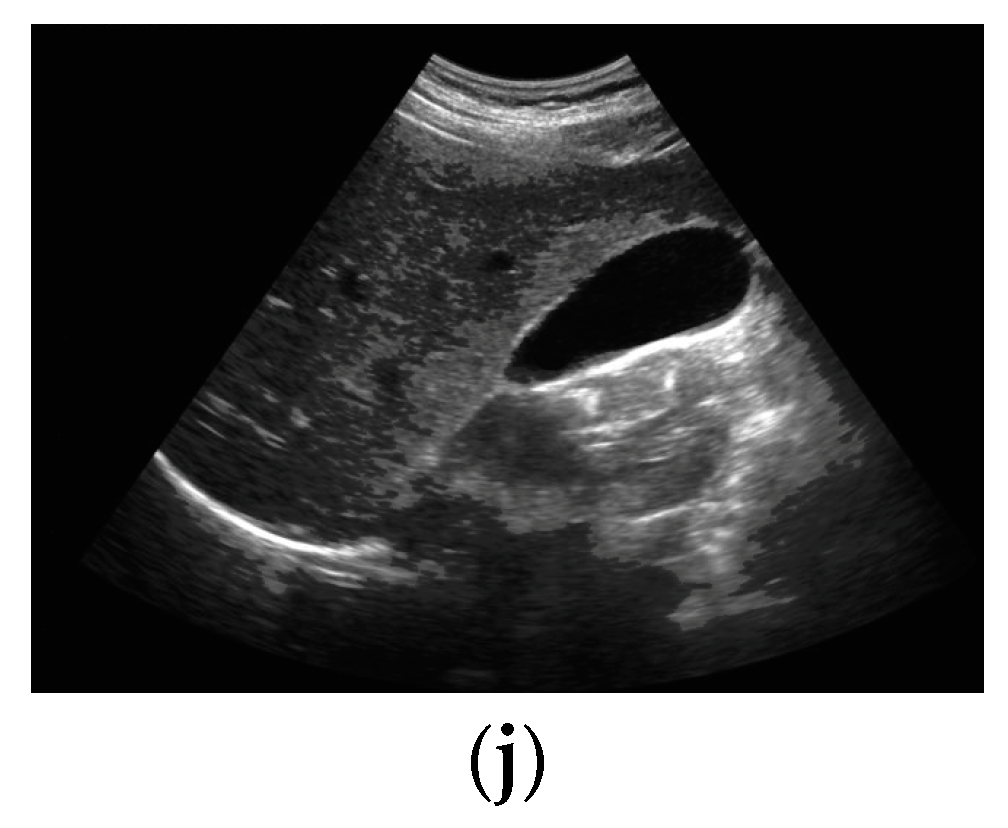

Figure 1.

GB diseases (a–i): (a) gallstones, (b) abdomen and retroperitoneum, (c) cholecystitis, (d) gangrenous cholecystitis, (e) perforation, (f) polyps and cholesterol crystals, (g) adenomyomat osis, (h) carcinoma, (i) GB wall thickening, and (j) normal GB.